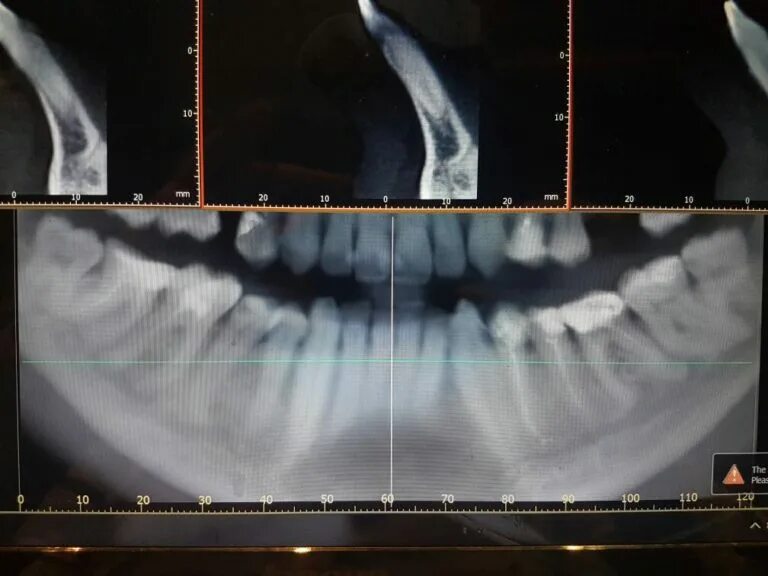

Зубы слева